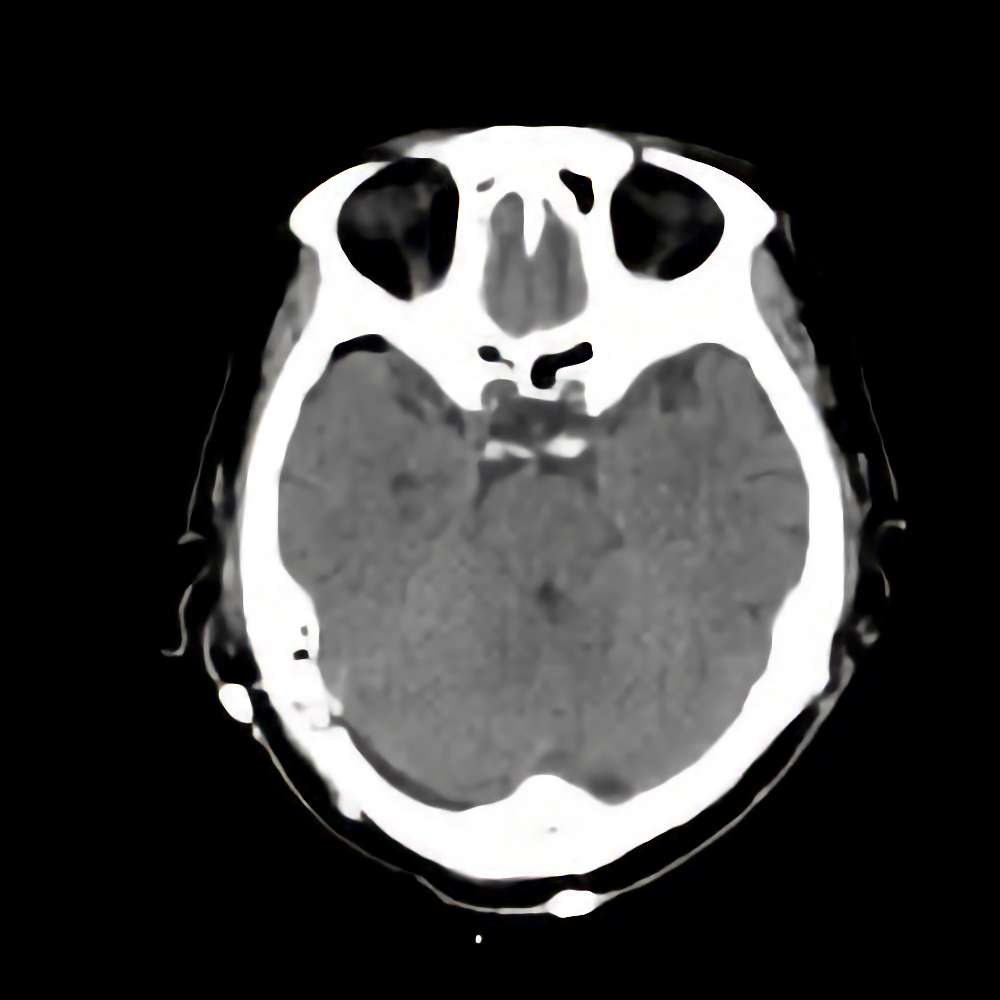

’15_55

'15年5月

70代

脳腫瘍

断層撮影

手術前

1

手術前2

手術後